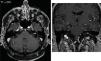

Results40 patients were included. The range age was 36–80 years. The most frequent reason for request the MRI was hearing loss (52.5%). Neuroradiologist without IVC found 82.5% of extraotic pathology and 17.5% of otic pathology, highlighting the neurinoma of the VIII pair (7.5%); ossifying labyrinthitis, retrofenestrated otosclerosis and cholesteatoma. After IVC administration, findings were similar. The resident identified otic pathology in 5% in baseline sequences and 20% using CIV. The interobserver correlation using IVC was excellent (0.97), but weak without IVC (0.52). There was a correlation between the reasons for request the MRI and the findings in the ears, both in protocols without IVC (p=0.004) and in protocols with IVC (p=0.002).

ResultadosSe incluyeron 40 pacientes. El rango de edad fue de 36-80 años. El motivo de solicitud más frecuente fue hipoacusia (52,5%). El neurorradiólogo sin CIV encontró un 82,5% de patología extraótica y un 17,5% de patología ótica, entre las que destacaba un neurinoma del VIII par (7,5%); también laberintitis osificante, otosclerosis retrofenestrada y colesteatoma. Tras la administración de CIV, los hallazgos fueron similares. El residente identificó patología ótica en el 5% en las secuencias basales y un 20% usando CIV. La correlación interobservador usando CIV fue excelente (0,97), pero débil sin CIV (0,52). Existió correlación entre los motivos de solicitud y los hallazgos en los oídos, tanto en los protocolos sin CIV (p = 0,004) como en los protocolos con CIV (p = 0,002).